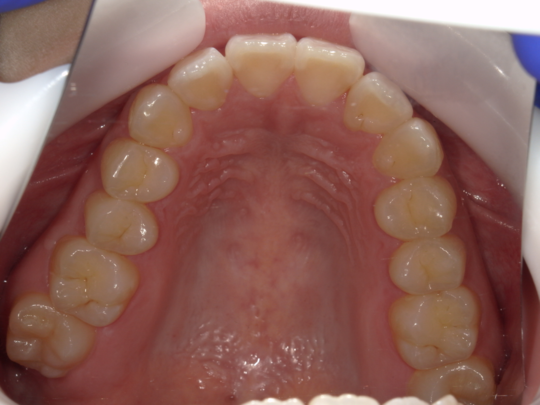

実例写真①

矯正前(上の歯)

矯正後(上の歯)

治療説明 歯科矯正でも目立ちにくい矯正方法です。透明に近いマウスピース型の矯正装置(アライナー)のため、歯に装着しても目立つことなく歯並びを矯正することが出来ます。また、一人ひとりの合わせて矯正装置を作製いたします。

治療期間 7か月

治療費用300,000 円

治療の副作用(リスク)歯の動き方には個人差があり、予想された治療期間が延長する可能性があります。。マウスピースの使用状況、矯正歯科治療には患者さんの協力が必要であり、それらが治療結果や治療期間に影響します。